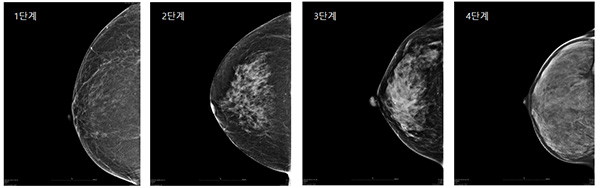

치밀 유방

치밀 유방이란 유선조직의 양이 상대적으로 많아 유방 속의 밀도가 높은 유방을 말합니다.

유방의 치밀도는 일반적으로 1단계에서 4단계로 나누어 보는데 , 3단계 이상의 치밀 유방은 유방 촬영 검사 시 유방의 50% 이상이 하얗게 나오는 경우입니다. 폐경 전 여성의 80%가 치밀 유방입니다.

치밀 유방 자체가 질환은 아니지만 유방암 발생 위험을 증가시킬 수는 있습니다.

유방촬영검사는 유방의 석회화나 혹을 발견하는데 효과적인 검사지만 , 치밀 유방에서는 석회화나 혹이 잘 보이지 않아 유방암을 발견하기 어려울 수 있습니다.